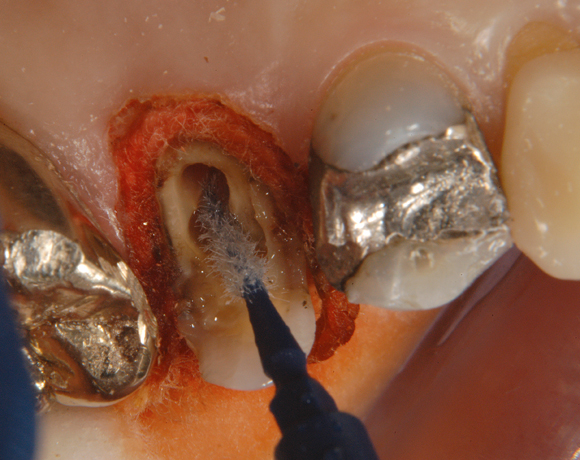

Ein Projekt aus dem Jahr 2003